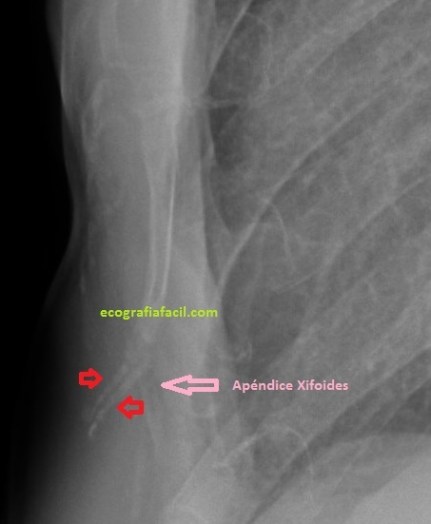

Cuando el/la paciente llega a la sala exploramos la zona de interés y solemos encontrar que el apéndice xifoides está posicionado hacia anterior como vemos en la imagen 1. Lo ideal es realizar localización en corte axial para poder descartar una apéndice bífido, es una anatomía variable, en este caso te presento un apéndice cuya disposición es bífida, puedes repasar aquí los diferente tipos que podemos encontrar.

En la imagen 2 se observan claramente dos líneas que se angulan hacia anterior. Esas dos imágenes, ecográficamente corresponden a la imagen 3…

Se evidencia una imagen donde el apéndice xifoides parece terminar en dos, bífido. Lo puedes apreciar como dos imágenes hiperecogénicas señaladas con flecha rosa, a niveles distintos, la izquierda más anterior que la derecha. En el corte longitudinal de ambas terminaciones observamos esto (imagen 4 y 5)